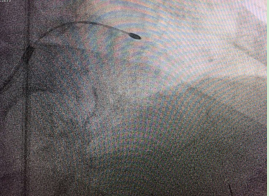

術(shù)前

術(shù)前,介入專家首先對陳大爺進(jìn)行了冠脈血管內(nèi)超聲檢查,明確血管內(nèi)結(jié)構(gòu)以及鈣化病變位置和嚴(yán)重程度。然后將帶有鉆石顆粒的高速旋磨頭送入患者血管內(nèi)的鈣化部位,在醫(yī)生的精細(xì)操作下,位于血管內(nèi)的磨頭便以每分鐘10多萬次的轉(zhuǎn)速開始高速旋轉(zhuǎn),根據(jù)“差異性切割”(即只針對嚴(yán)重鈣化和纖維化的病變斑塊組織而不損傷正常組織)原理,將阻塞血管的動(dòng)脈斑塊迅速磨成極其微小的顆粒,隨血液循環(huán)至血管遠(yuǎn)端并通過毛細(xì)血管床吸收。經(jīng)過幾次旋磨后,阻塞血管腔的鈣化斑塊被逐漸消除,在進(jìn)行球囊擴(kuò)張之后,在兩支血管內(nèi)順利植入四枚支架,成功開通血管,手術(shù)時(shí)間總共用時(shí)1個(gè)多小時(shí)。

“由于病人的左主干及三支血管均有不同程度的病變,為了安全起見,我們采取了分步實(shí)施手術(shù)的原則,先處理了兩支鈣化較嚴(yán)重的血管?!痹∪乇硎?,令人欣慰的是,第一次手術(shù)后老人胸悶胸痛癥狀迅速緩解,術(shù)前在醫(yī)院過道上走二三十米就感到明顯胸痛,術(shù)后第二天便在病房內(nèi)隨意走動(dòng),術(shù)后第三天就可以到醫(yī)院附近走動(dòng)而無明顯胸悶胸痛等不適。

術(shù)后